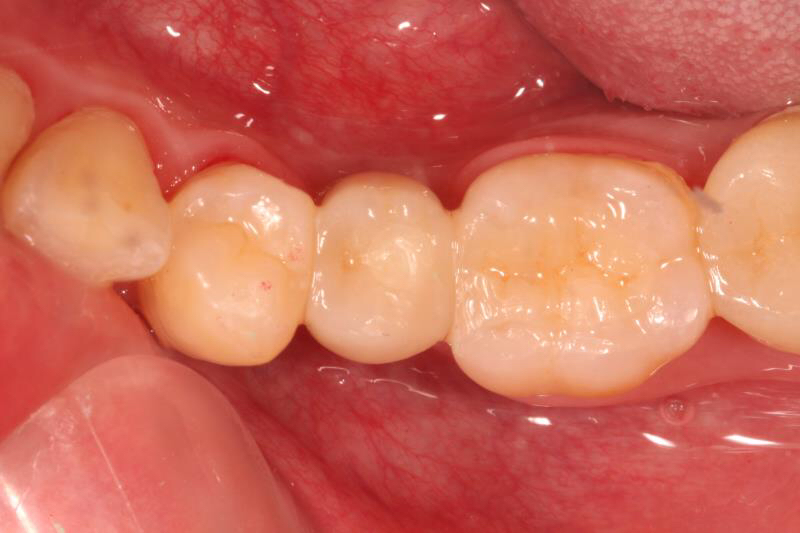

回到主题,老卢为这位小伙子采用即拔即种的方式,由于骨量条件尚可,植体植入后直接上愈合基台,这样就可以让患者提前了戴牙时间,早一些用上这颗牙齿吃东西。希望小伙子能体会老卢的良苦用心,以后好好保护自己的牙齿。